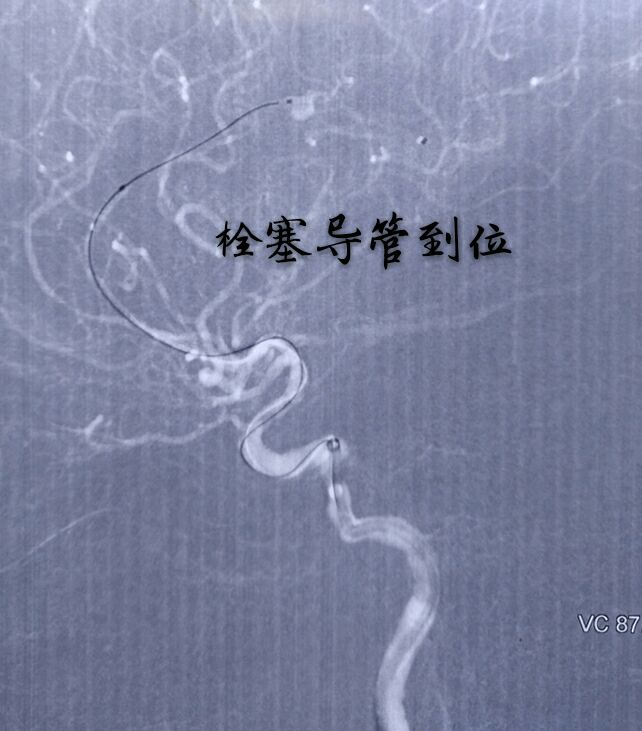

病例十一:大脑前动脉A4段动脉瘤,宽颈,载瘤动脉纤细

支架辅助下动脉瘤致密栓塞,难点:动脉瘤位置远,通路迂曲,使用8F GUIDING置于颈内动脉C2段,内套6F Navien置于床突段完成